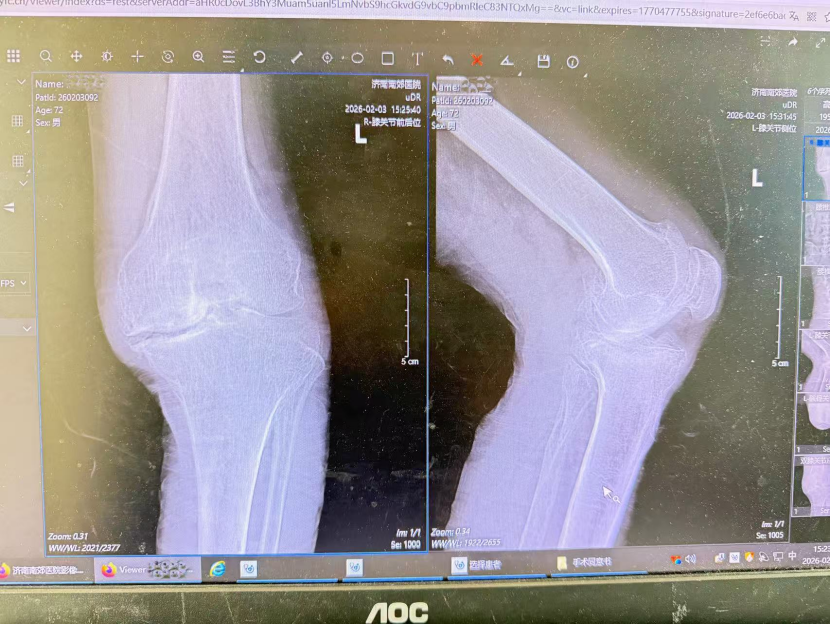

72岁患者刘先生(化名)10余年前无明显诱因出现双膝关节疼痛,久走后加重,休息缓解,左侧为重。曾接受小针刀治疗效果欠佳,自行间断贴敷药物、口服止痛药,短期有效但长期不佳。病情渐进性加重,现活动明显受限,不能长距离行走,下蹲、起身困难,严重影响日常活动。为求进一步明确诊断与治疗,来到济南南郊医院骨科门诊,经初步检查以“双侧膝关节骨性关节病”收入院。

骨二科杨学良主任团队立即对刘先生全面评估,询问病史并查体。专科查体发现患者双侧膝关节肿胀,左侧明显,膝关节周围压痛阳性,内侧关节间隙为重,双侧股四头肌轻度萎缩。结合病史与体征,杨主任团队评估后认为手术是改善症状、恢复关节功能的有效手段。经与患者及家属沟通,确定实施左侧人工全膝关节置换术,以替换受损关节面,缓解疼痛,恢复功能。